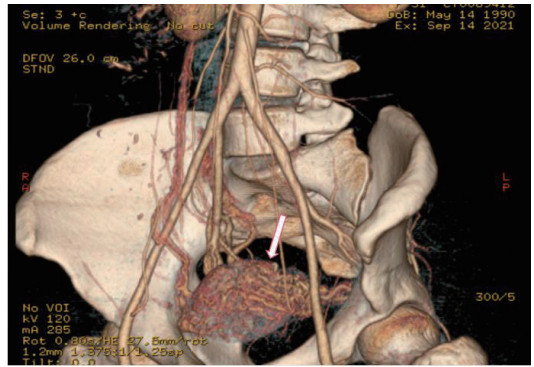

2.4 CTA检查与DSA检查非保守治疗患者中26例患者行CTA检查(图 4),24名提示UAVF, 诊断敏感率为92%。联合TVDU可确诊25名,既CTA、超声联合诊断UAVF的敏感率为96%。非保守治疗的34例患者DSA检查均诊断UAVF。

| 图 4 子宫动脉CTA血管造影:子宫动脉血管迂曲增粗成团(白色箭头) |

CTA对动脉和静脉来源出血均敏感[14],可显示UAVF畸形血管三维空间结构[6],诊断敏感度达92%,特异度达100%,如联合TVDU,敏感度可高达96%,是理想的诊断方法。